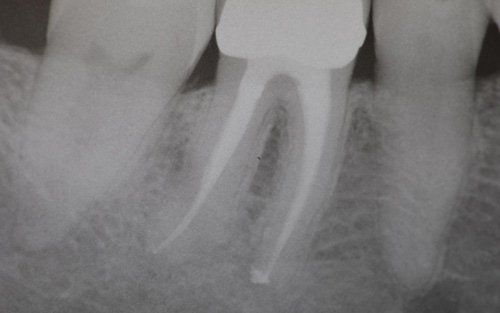

This treatment should be reserved for teeth that have irreversible pulp pathology (the nerve of the tooth) or an infection of the dental canals that has caused an abscess (acute apical periodontitis) or a granuloma (chronic apical periodontitis). While in the first two cases the tooth is very painful and the patient immediately seeks the dentist, the case of the chronic form is often silent, and therefore the patient may not notice anything for a medium to long period of time. In such conditions, it is only an X-ray image, taken during routine check-ups, that detects its presence. Root canal therapy can be completed by placing a latest-generation post inside the canal, as a means of retaining the material used for the reconstruction of the tooth. It will be up to the clinician to decide whether or not the restoration requires this additional anchoring system.